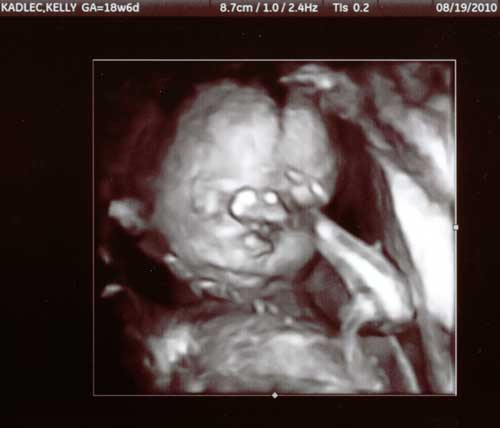

19 August 2010

At our 19 week ultrasound appointment,

the ultrasound tech turned on the 3D feature

to show us some images of his face.

hand

he looks a little camera shy with his hand in front of his face

cord